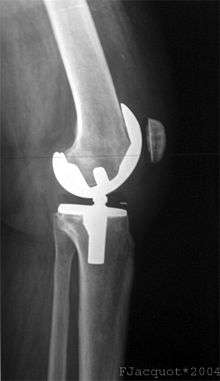

Knee replacement surgery can be performed as a partial or a total knee replacement.[2] In general, the surgery consists of replacing the diseased or damaged joint surfaces of the knee with metal and plastic components shaped to allow continued motion of the knee.

Femoral replacement

A round ended implant is used for the femur, mimicking the natural shape of the joint. On the tibia the component is flat, although it sometimes has a stem which goes down inside the bone for further stability. A flattened or slightly dished high density polyethylene surface is then inserted onto the tibial component so that the weight is transferred metal to plastic not metal to metal. During the operation any deformities must be corrected, and the ligaments balanced so that the knee has a good range of movement and is stable and aligned. In some cases the articular surface of the patella is also removed and replaced by a polyethylene button cemented to the posterior surface of the patella. In other cases, the patella is replaced unaltered.